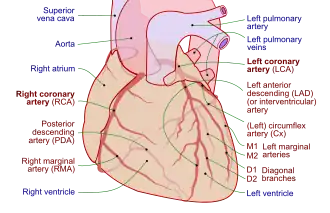

A coronary angiogram showing the circulation in the left coronary artery and its branches. | |

| Coronary arteries providing blood to the heart. The blood vessels originate from the aorta and surround the heart. | |

Showing the coronary arteries that are subject to narrowing - resulting in reduced blood supply to the cardiac muscle. | |